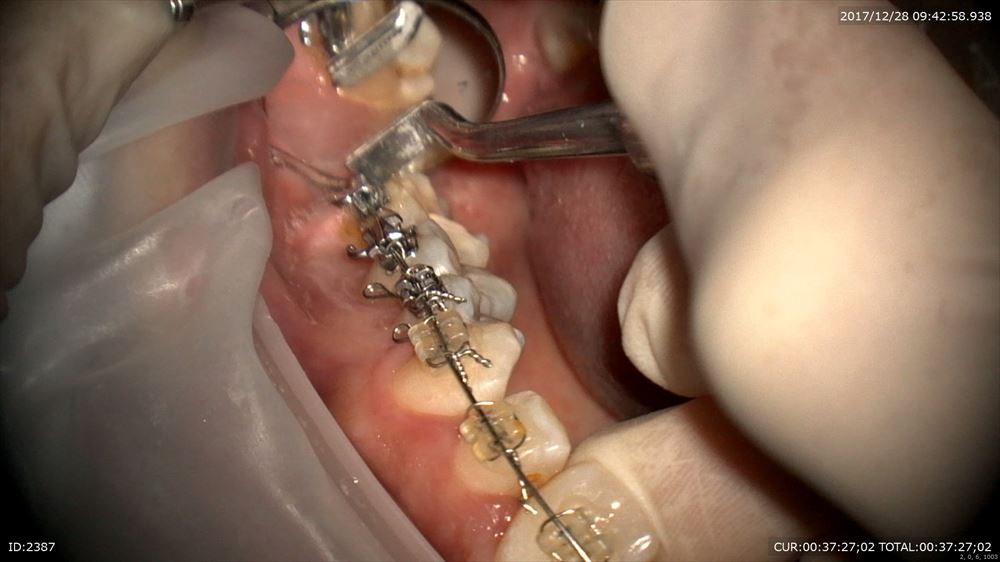

矯正治療の終盤の患者さま 抜歯スペースも埋まりこれから最終ステージ:フィニシングステージへはいります。

犬歯関係がよくないのでこんな機械で針金に熱を加えニッケルチタンワイヤーを曲げていきます。

左下の犬歯にオフセット

トルクも確認

なるべくニッケルチタン系のワイヤーを使うことで弱い力で歯を動かしていきます。痛みが少ない矯正が可能になります。来年春に外す予定です!!